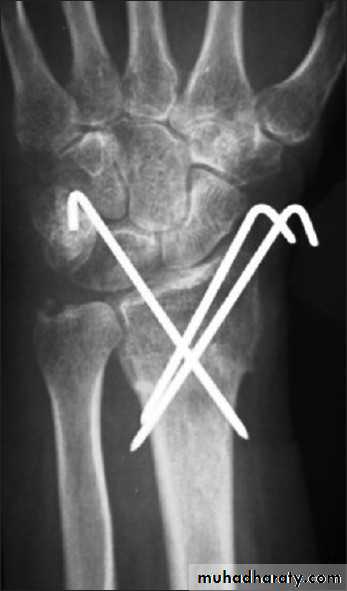

INTERNAL FIXATION

Indications

advantages